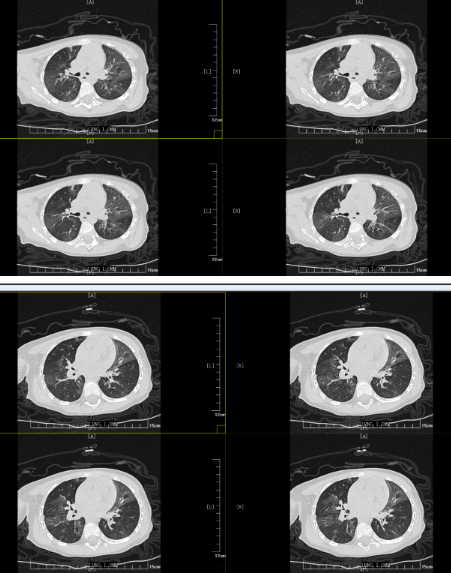

但胸部CT的結(jié)果表明小丸子的肺內(nèi)病變比較重,同時通氣也不均勻,確實存在堵塞,可這個"堵住氣管的東西”到底是什么,還得在支氣管鏡檢查下才能知道。在和小丸子的父母詳細溝通病情后,入院第二天一早,小兒內(nèi)科田恬主任便為其進行了無痛電子支氣管鏡檢查。